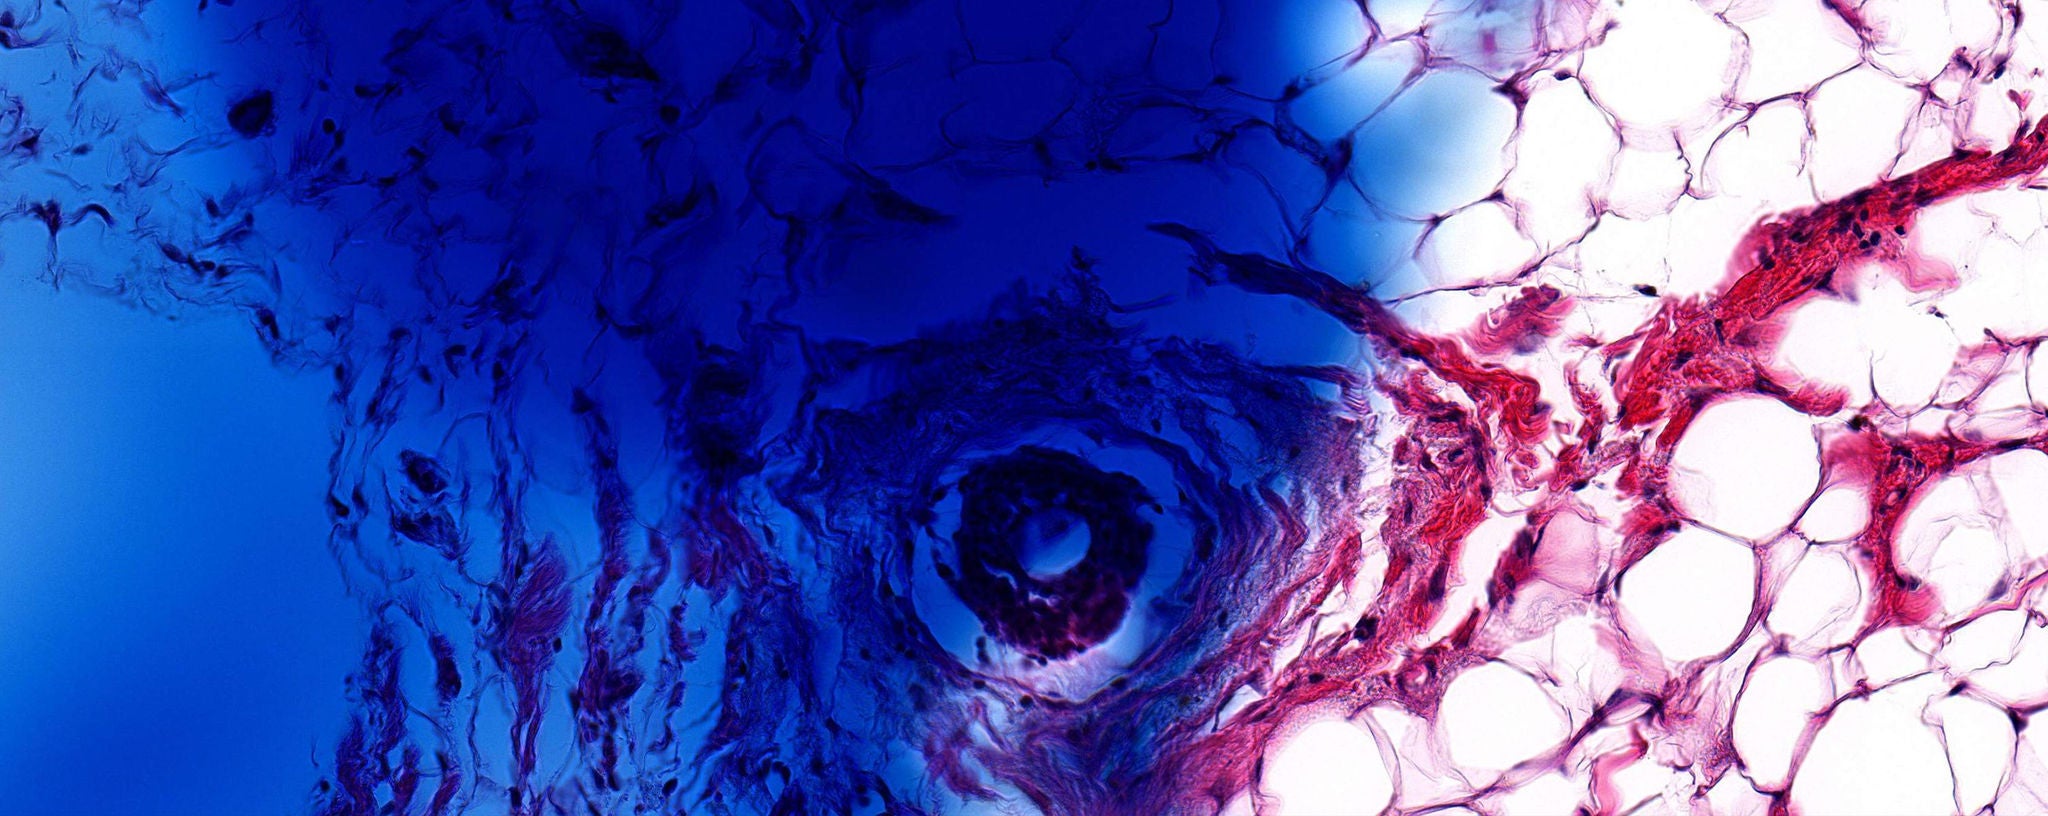

Every two years, ACS sent participants a follow-up questionnaire, and if someone reported that they had breast cancer, their hospital would send tumor samples to ACS. The samples were made by soaking the removed tumor in a solution that stops cellular activity, putting it in a block of wax, taking a very thin slice out of the block, staining the slice to show the different parts of the cells, and then putting the slice in a glass slide.

A closeup image of a cancer cell.

The next step was to scrub the tissue slides of any inconsistencies that could skew the analysis. A lot has changed since 1992 in terms of how pathologists treat the slides. In the 90s, pathologists mixed the tissue dye by hand, which means there’s been a lot of color variations in the slides over the years. “We had some slides that were a light pink and some that were a dark purple,” says Gaudet. Also, some pathologists would write directly on the slides with Sharpies, circling a tumor or making notes.

The machine created some clusters that the team understood, like identifying the grade of cancer, which validated that the machines were on track. “But there are also new patterns that we’re not yet unable to understand why they were clustered, which was the goal,” says Gaudet. “For example, clusters two and three—well, to my eye they look exactly the same but that’s the whole premise of the project, for the machine to identify differences that the human eye can’t.”

Closeup of different cell images.